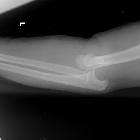

Most elbow dislocations are closed and are most frequently posterior (sometimes posterolateral or posteromedial) although anterior, medial, lateral and divergent dislocations are also infrequently encountered). Posterior dislocations typically occur following a fall onto an extended arm, either with hyperextension or a posterolateral rotatory mechanism .

Plain radiograph

The dislocation is usually obvious, especially if adequate AP and lateral views are obtained, however, the challenge is in identifying associated fractures.

Although rarely required in practice, a line drawn along the anterior margin of the humerus (anterior humeral line) and one along the long axis of the radius should intersect near the center of the capitellum .